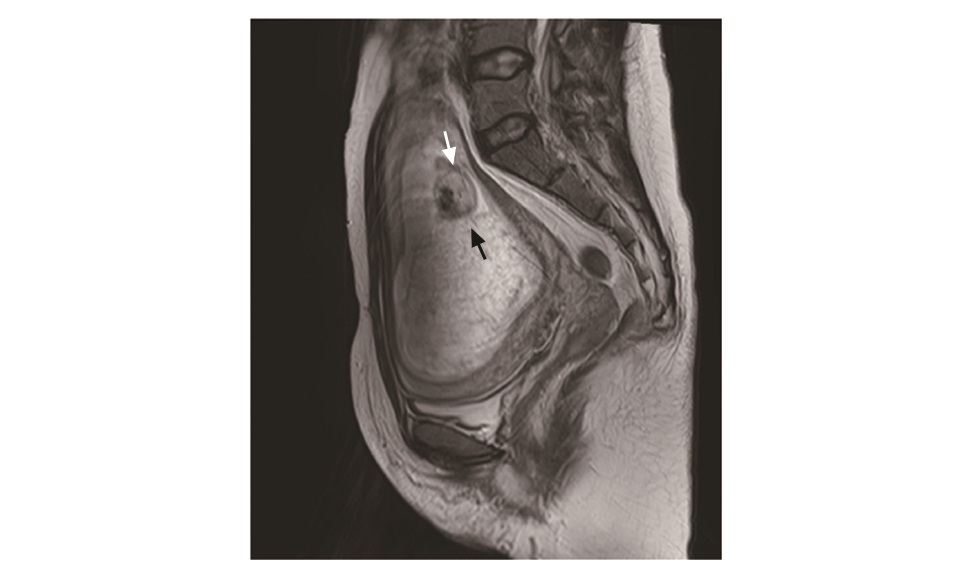

Abstract: Hydatidiform mole is a benign gestational trophoblastic disease. Twin pregnancy with hydatidi-form mole and a coexistent fetus is extremely rare. The diagnosis is usually delayed and the pregnancy is often terminated due to severe vaginal bleeding or other complications. There are few guidelines for termination methods. Here we report a case of successful labor induction and vaginal delivery of twin pregnancy with hydatidiform mole and a coexistent fetus at 16 weeks of gestation. The diagnosis, treatment principles, and termination methods are discussed.